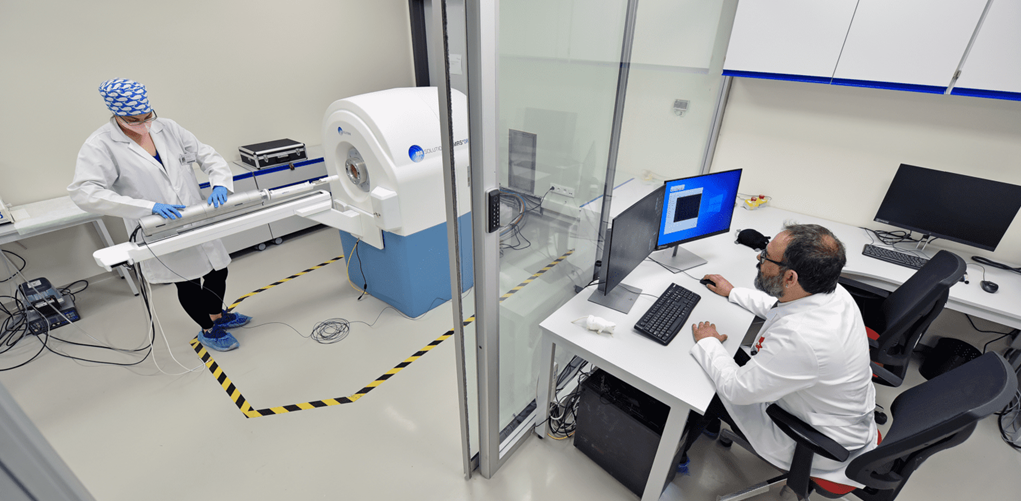

Field of Study: Magnetic resonance imaging techniques (MR spectroscopic imaging (MRSI), arterial spindle labelling (ASL), diffusion tensor imaging (DTI), etc.) are used to identify anatomical, physiological and biochemical changes due to brain diseases, classification of medical image data for disease diagnosis using machine learning and deep learning methods, and image enhancement (super enhancement).To identify anatomical, physiological and biochemical changes due to brain diseases using magnetic resonance imaging techniques (MRI), classification of medical image data for disease diagnosis using machine learning and deep learning methods and image enhancement (super resolution), to accelerate routine MRSG techniques used in the clinic, To develop quantitative molecular MR imaging techniques for more sensitive and accurate data acquisition and processing, to develop modelling and analysis methods to create MR parametric maps, to develop user-friendly data analysis interfaces, and to produce phantoms that mimic brain chemistry and anomalies.